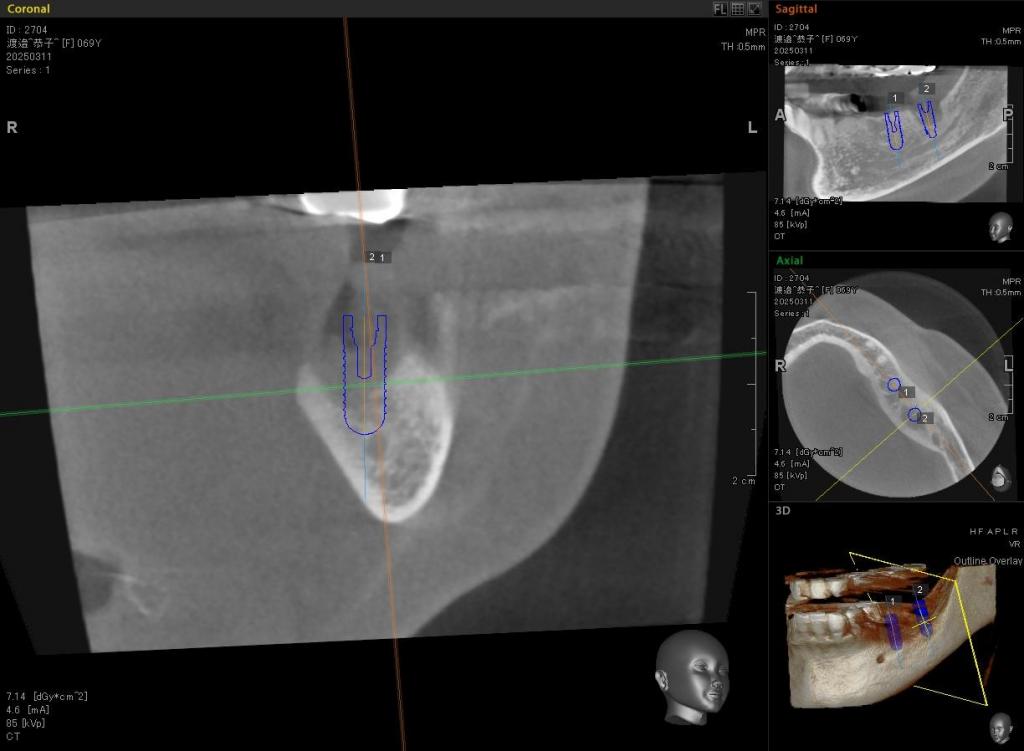

治療中写真

- CTを撮影しても、同部の骨は大きく吸収、喪失していました。

しかしGBRという方法を用いて、インプラントは可能と判断しました。